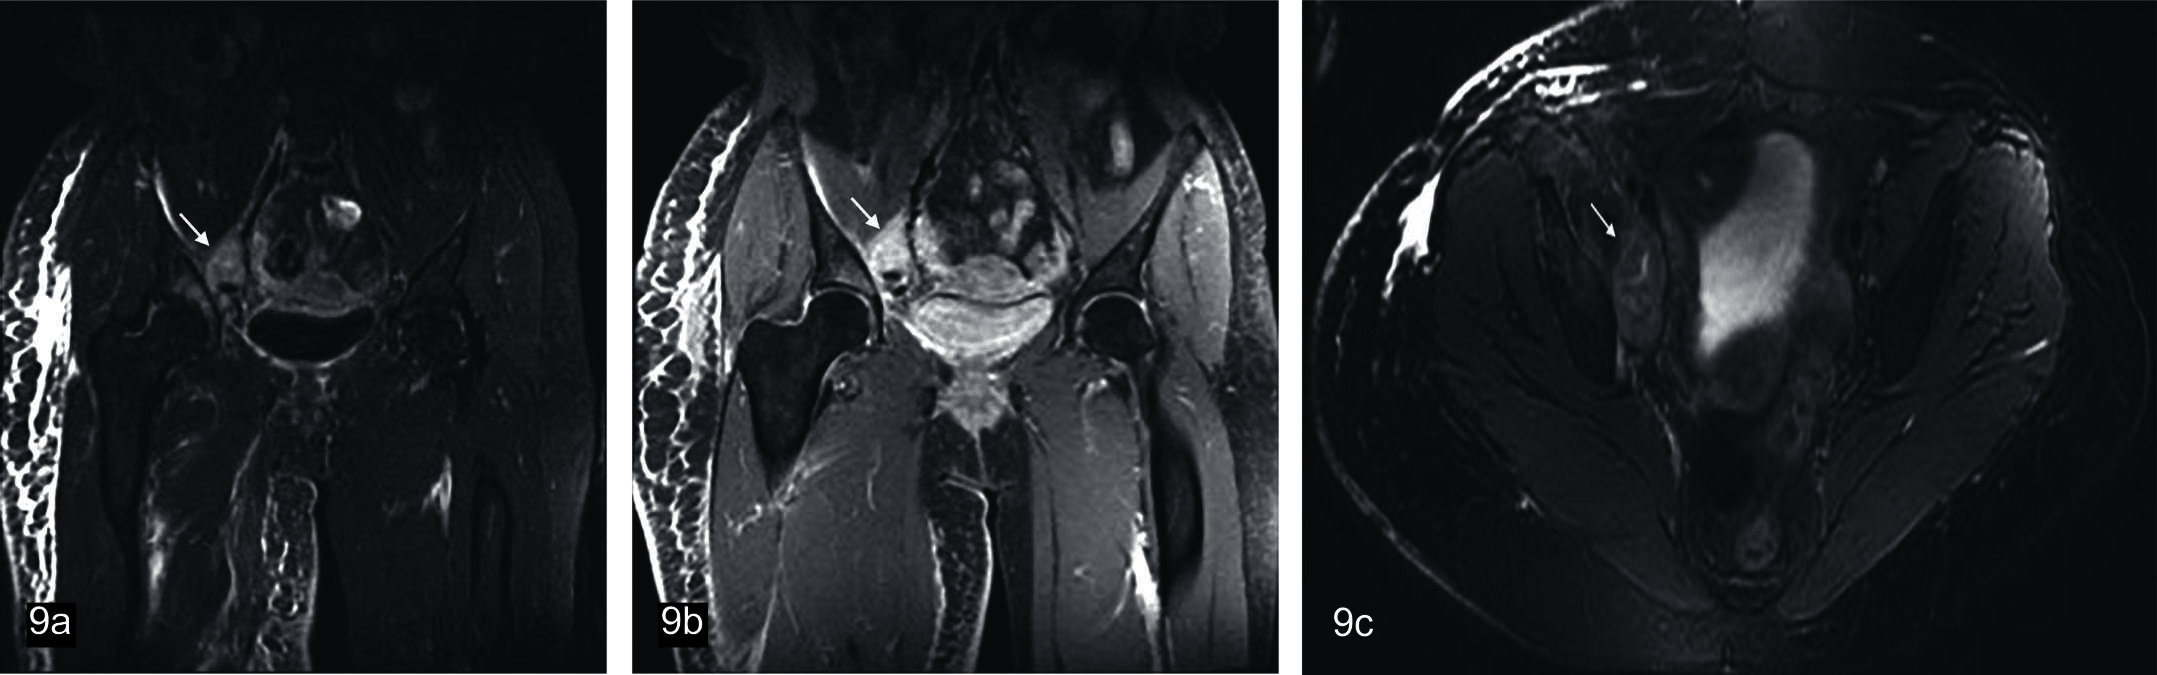

Figura 9

Schwannoma maligno.

Paciente femenina de 65 años de edad. Secuencias neurográficas IDEAL: Se observa en topografía del nervio obturador interno derecho formación fusiforme, de bordes irregulares, heterogénea (flechas); presenta señal (a) hiperintensa en ponderación T2 FAT SAT, (b) refuerzo irregular en ponderación T1 FAT SAT con contraste; (c) Secuencia axial T2 FAT SAT.